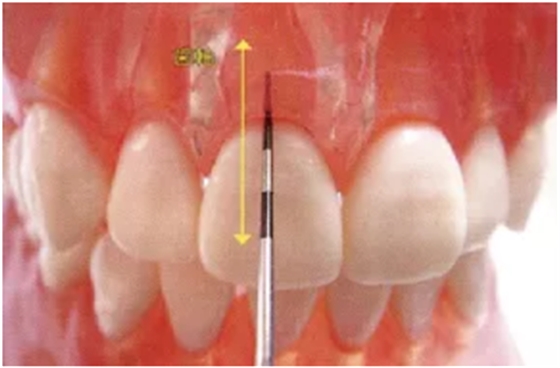

牙周探针的工作尖始终与牙体接触,将工作尖从袋底上提1~2mm的幅度进行步行式探诊。